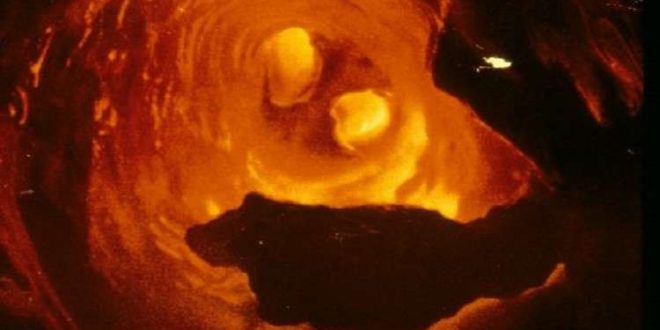

ويعد مرض تصلب الشرايين وأمراض القلب الأخرى المرافقة وفقا لإحصائيات منظمة الصحة العالمية، أحد الأسباب الرئيسية لتطور النوبات القلبية، وبالتالي الوفيات في معظم دول العالم، حيث يبدأ هذا المرض عادة بتراكم لويحات الكوليسترول على جدران الشرايين وبعد مضي فترة يزداد سمك هذه الجدران وتفقد مرونتها.